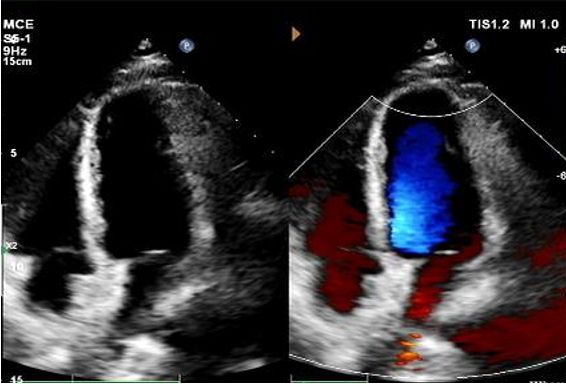

Today, we share a remarkable case highlighting 1-year post-op outcomes of MemoSorb in treating a complex long-tunnel PFO (12mm length, 1.4mm width), with a focus on serial echocardiographic evidence of device degradation and clinical symptom resolution.

Wichtige Ergebnisse der Follow-up-Bildgebung

Tag 1 bis 9 Monate:

Kein Rest-Shunt beobachtet.

Allmähliche Verringerung der Geräte echogenität.

1-jähriges Echo:

No visible disc structures – replaced by 8mm tissue thickening at the septal implant site.

Zero residual shunt (rest or post-Valsalva).

Komplette Absorption des Geräts bestätigt.